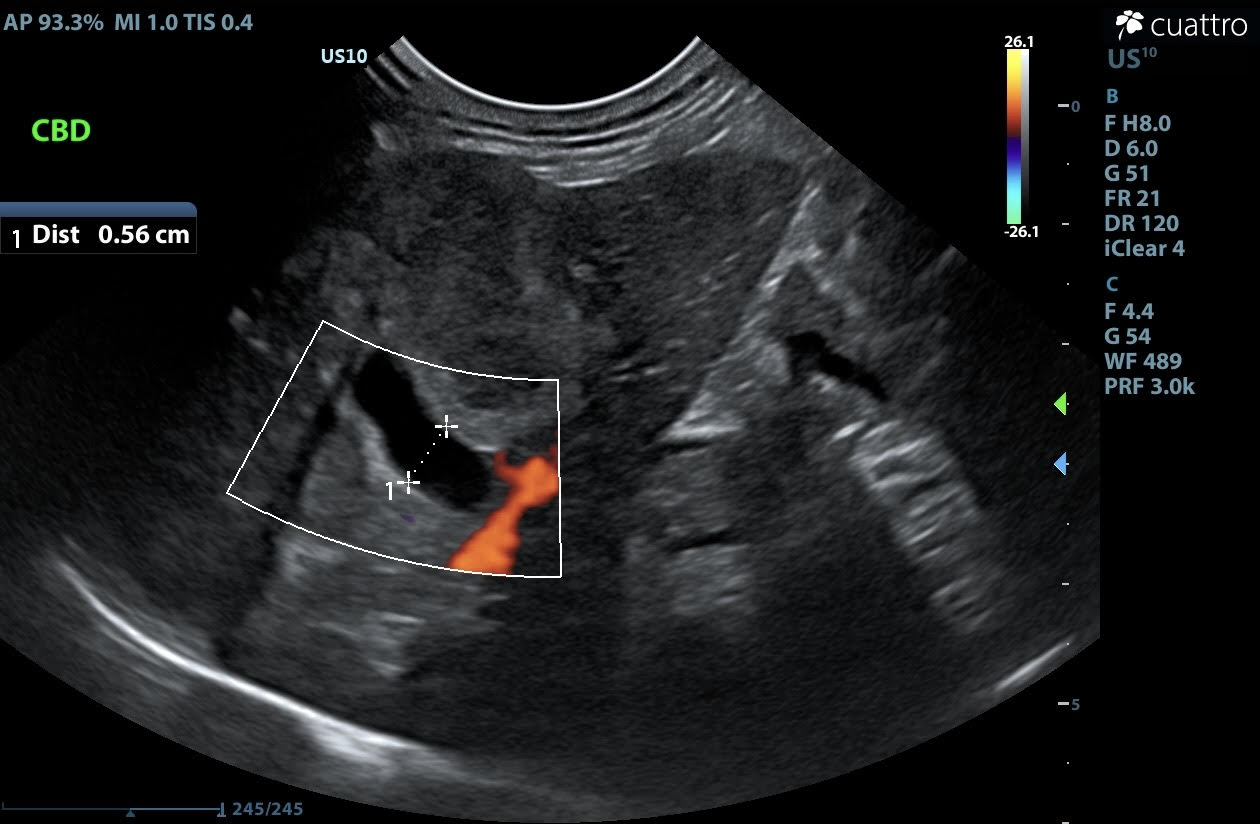

Liver - In the right liver, there is an irregularly marginated, capsule-deforming, heterogeneously hypoechoic mass measuring approximately 2.7 x 2.9 cm. Adjacent to this mass, there is an oval-shaped structure that is heterogeneously hypoechoic at the center with a hyperechoic margin, measuring approximately 1.2 x 1.5 cm. This structure may represent the gallbladder (expected) v. a second, coalescing mass. The common bile duct is dilated (5.6 mm diameter). The remaining liver parenchyma has multifocal, round, mildly capsule-deforming, hyperechoic nodules measuring up to 0.4 x 0.5 cm.

Image 1: Liver mass in sagittal (between calipers) with an anechoic tubular structure extending caudally from the mass.

Image 2: Lack of color flow confirming the anechoic tubular structure is not vascular. This structure is the dilated common bile duct (CBD; between calipers).

Image 3: Inflamed gallbladder v. second coalescing mass.